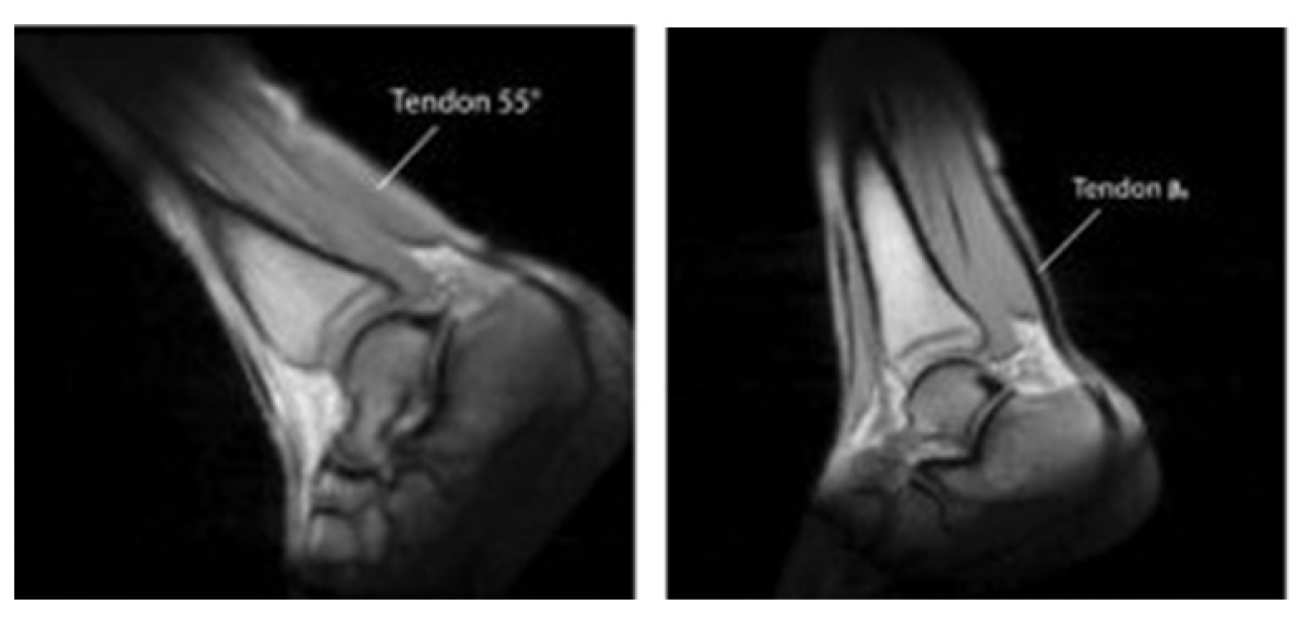

Many significant tissues containing collagen have short relaxation times which make them very hard to image using conventional MRI.

Changing the tissue orientation relative to the direction of the magnetic field can largely resolve this issue, and we have developed a magnet system which permits such changes.

Pairs of anatomical images obtained at different angle of the main field, arrows are used to mark tissues experiencing signal changes due to the magic angle effect.